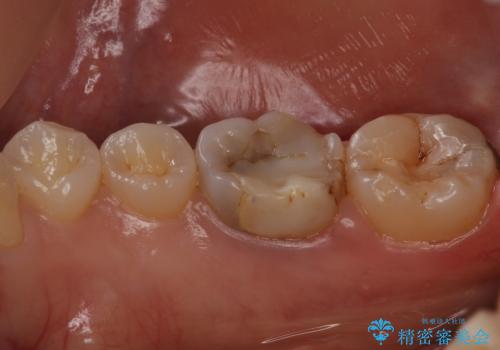

- 矯正前の虫歯治療です。

奥歯が樹脂の詰め物で継ぎ接ぎになっていることが確認されたため、今後の虫歯リスクを減らすために適合の良いフルジルコニアクラウンを入れていきます。

樹脂で継ぎ接ぎになった歯はそうでない歯と比べて虫歯になるリスクが高いです。

樹脂をすべて取り、虫歯も取り切った後に適合の良いクラウンを装着することで今後の虫歯リスクを減らすことができます。